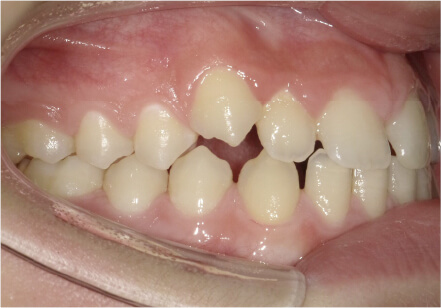

叢生の症例

41歳

女性

横から見た時のガタガタが気になる

カウンセリング・診断結果

インビザライン、正中は上11に合わせていく、抜歯・拡大装置・IPR・アタッチメントOK

治療内容・方法

アライナー矯正

術後の経過・現在の様子

クリアライナー使用

費用・治療期間

880,000円、7ヶ月